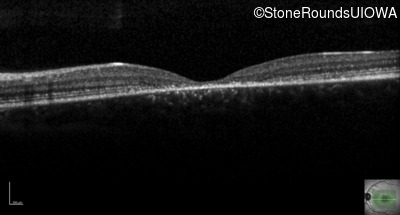

AR Stargardt Disease (IIA)

AR Stargardt Disease (IIA)

This 11 year old female first had difficulty seeing the blackboard at age 8. Later, she developed some photophobia.

| AR Stargardt Disease | ABCA4 | Gly1961Glu GGA>GAA, Arg212Cys CGC>TGC | Gly1961Glu GGA>GAA, Arg212Cys CGC>TGC | AR |